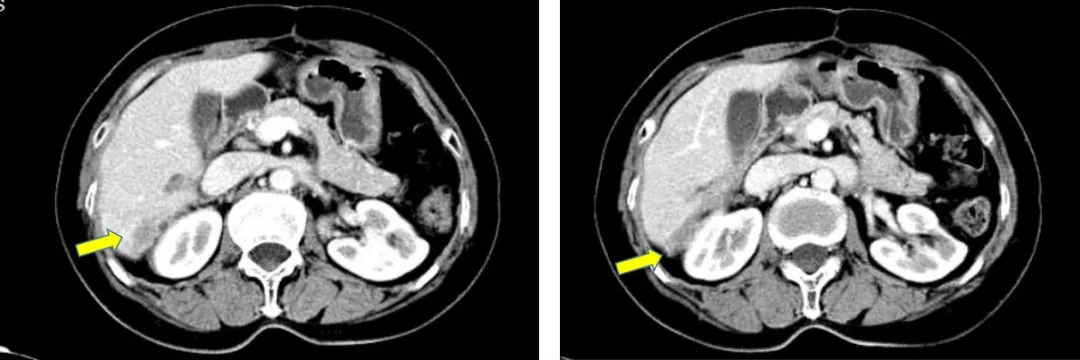

2017-10-26当地查CA125水平为46.3U/ml,2017-12-4我院查CA12水平为110.9U/ml,CT显示肝肾间隙及右肝包膜下片状影较前增大,考虑疾病复发。

患者不愿意接受手术,2017.12.15-2018.4.12行多西他赛+卡铂化疗6疗程。

CT检查结果